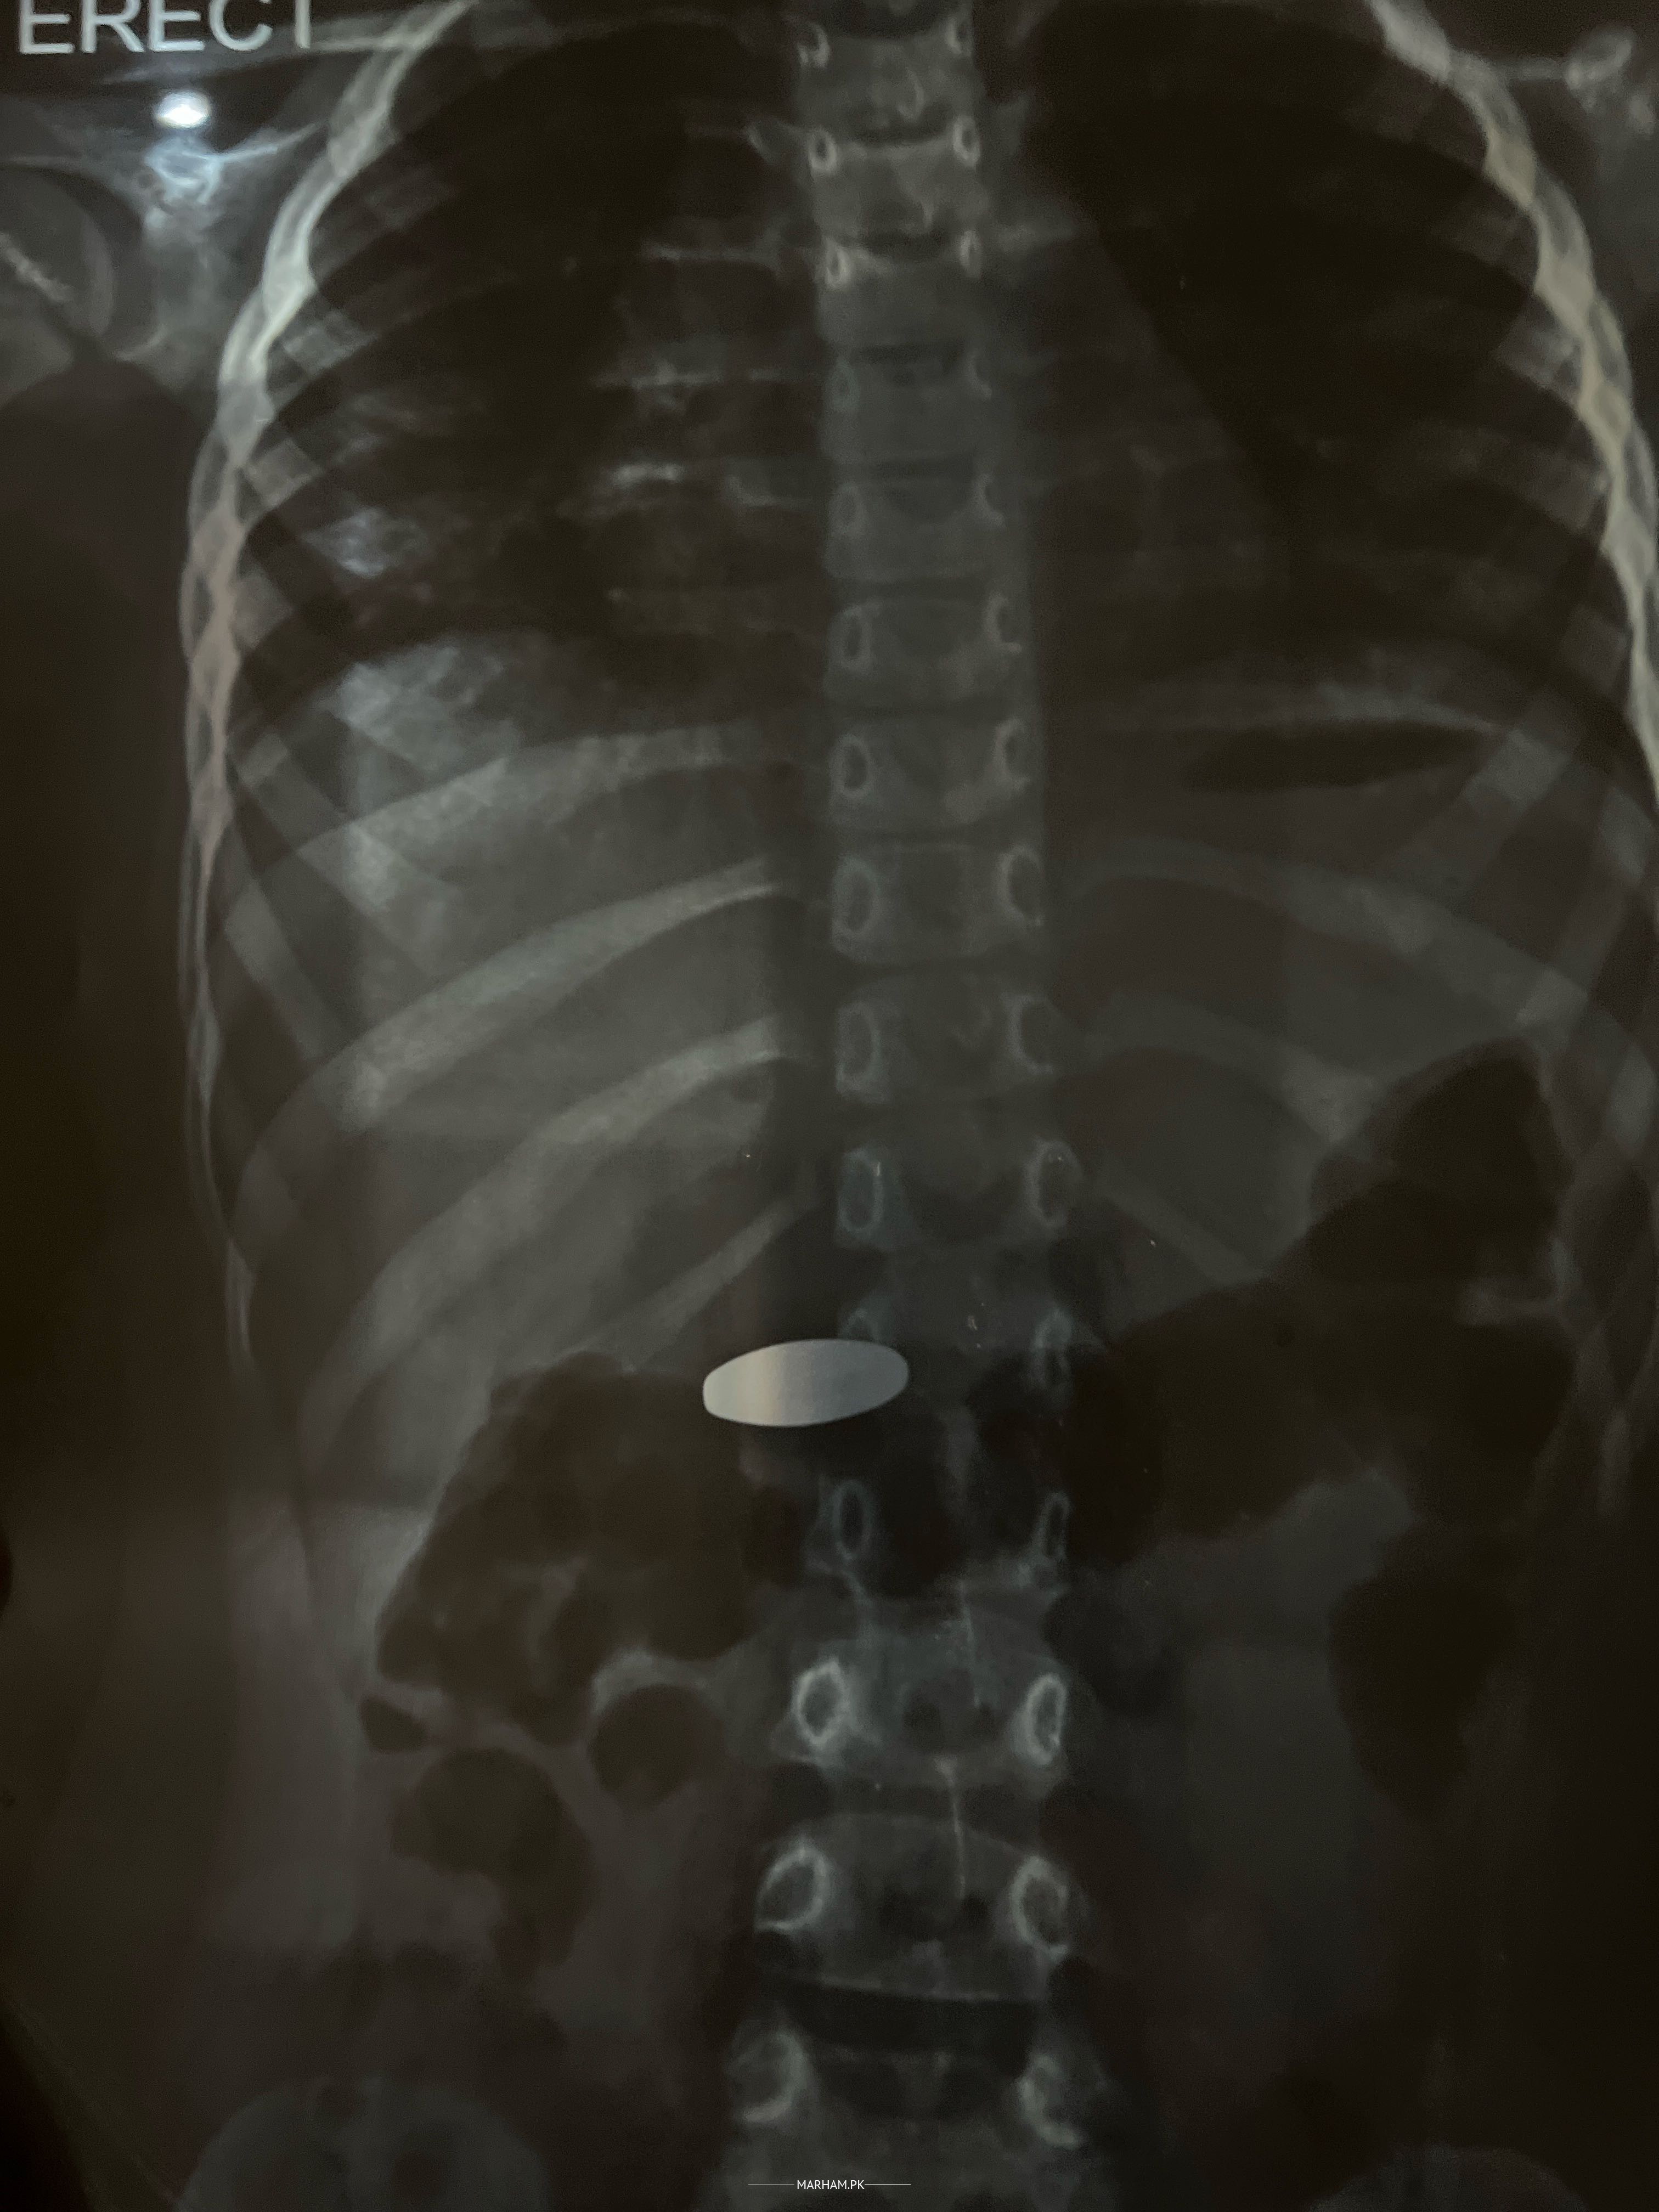

My daughter has swallowed magnet I took her to emergency had her x ray of abdomen dr said to repeat xray tomorrow morning I am very worried for her. Please help